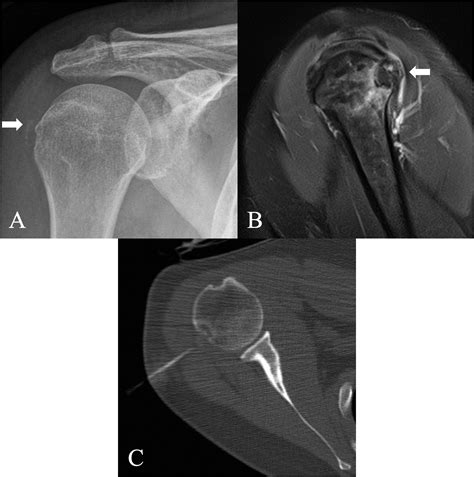

HADD can affect various joints, including the shoulder, elbow, wrist, hip, knee, and ankle. It can also occur in soft tissues such as tendons and ligaments. The most commonly affected areas are the shoulder and the wrist.

Diagnosing HADD involves a combination of clinical evaluation, imaging studies, and laboratory tests. The diagnostic process typically includes the following steps:

• Imaging Studies: X-rays, ultrasound, and magnetic resonance imaging (MRI) can help identify the presence of hydroxyapatite crystals and assess the extent of the deposits.

Imaging studies are particularly important in diagnosing HADD. X-rays can show calcifications in the affected areas, while ultrasound and MRI provide more detailed images of the soft tissues and joints. Laboratory tests can help rule out other conditions that may cause similar symptoms.